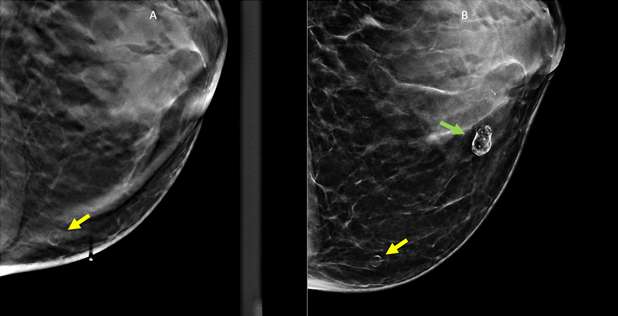

Mammographic Findings: On mammography, fat necrosis typically presents as a well-defined, round or oval mass with varying densities. Initially, it may appear as a radiolucent mass due to the liquefaction of necrotic fat. Chronic lesions may develop rim or “eggshell” calcifications; this appearance is benign when associated with history of trauma and does not require specific imaging follow-up or treatment. As fat necrosis evolves, fibrosis may develop in a spiculated or irregular morphology, which can present similarly on mammogram to breast carcinoma.3 In these cases, correlation with clinical history, close follow-up and/or biopsy may be necessary to distinguish benign fat necrosis from malignant breast masses.